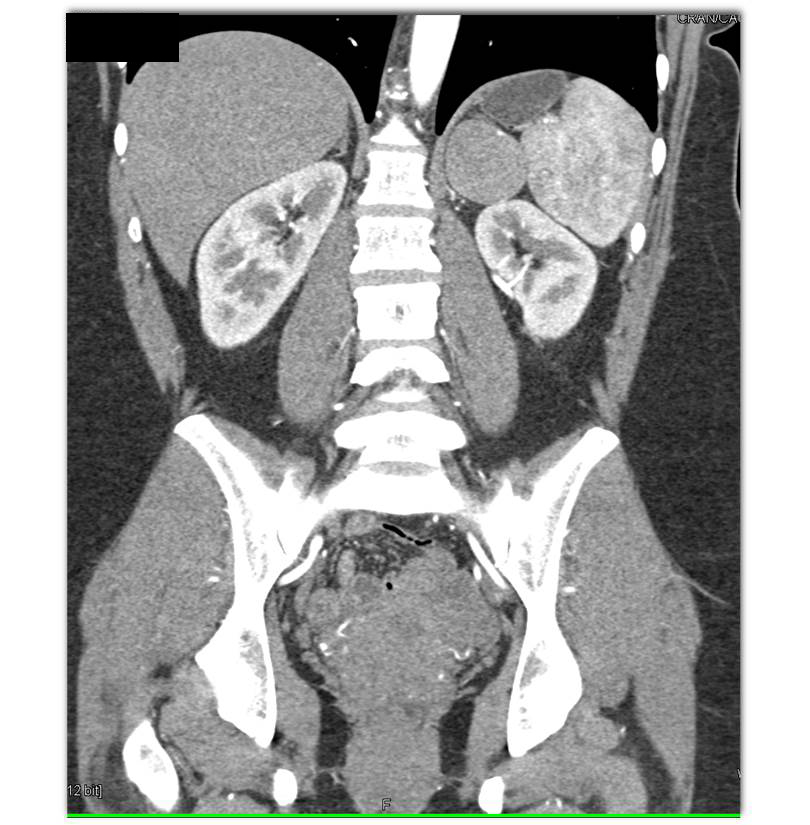

The least likely diagnosis for this 5cm left adrenal mass is?

adrenal adenoma

adrenal carcinoma

pheochromocytoma

adrenal lymphoma